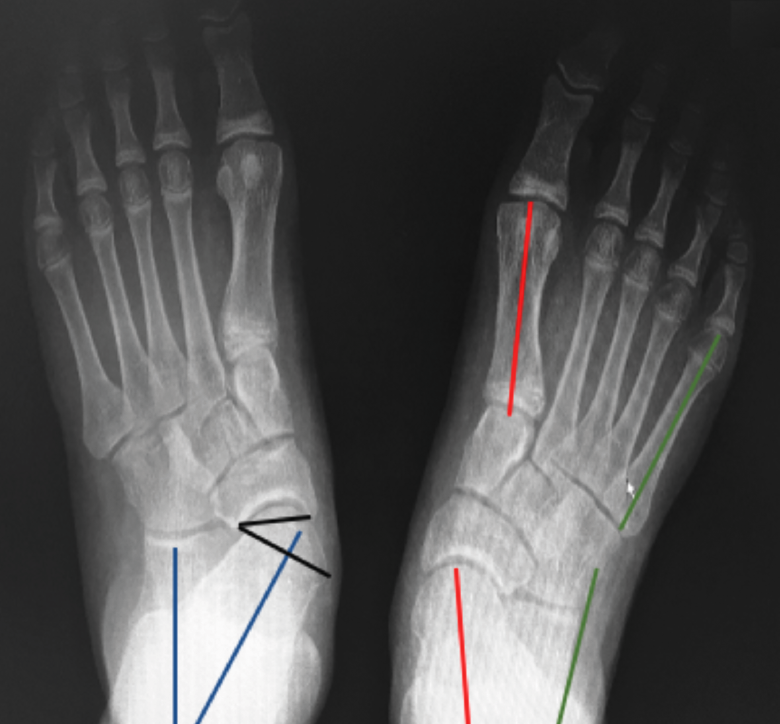

Radiografía dorsoplantar en carga (Figura 5)

Figura 5. Radiografía dorsoplantar en carga. Ángulo Kite (azul). Ángulo C5M (verde). Ángulo del eje del astrágalo y el eje del primer metatarsiano (rojo). Ángulo de descobertura talonavicular (negro).

- Ángulo astrágalo-calcáneo (AC) o de Kite (normal entre 20 y 30°): su aumento es el reflejo de la divergencia AC aumentada en el PPV de componente subtalar.

- Ángulo entre el borde lateral del calcáneo y el eje longitudinal del quinto metatarsiano (C5M): su alteración se correlaciona con la abducción del antepié, siendo su valor normal 0°.

- Ángulo entre el eje del astrágalo y el eje del primer metatarsiano (valores normales de 0 a 5°). Este ángulo es útil para determinar el componente de metatarso aducto. Asociado a una divergencia AC aumentada, orienta a un pie en serpentina o en Z.

- Valoramos la cobertura TN con el ángulo de descobertura TN (valores normales de 10°) o con el porcentaje de descobertura de la cabeza del astrágalo (si > 40%, indica deformidad en abducción severa)(7).

Radiografía lateral del pie en carga (Figura 6)

Figura 6. Radiografía lateral del pie en carga. A: pie normal; B: pie plano. Ángulo de Meary (rojo). Ángulo de Costa-Bartani (azul). Calcaneal pitch angle (negro).